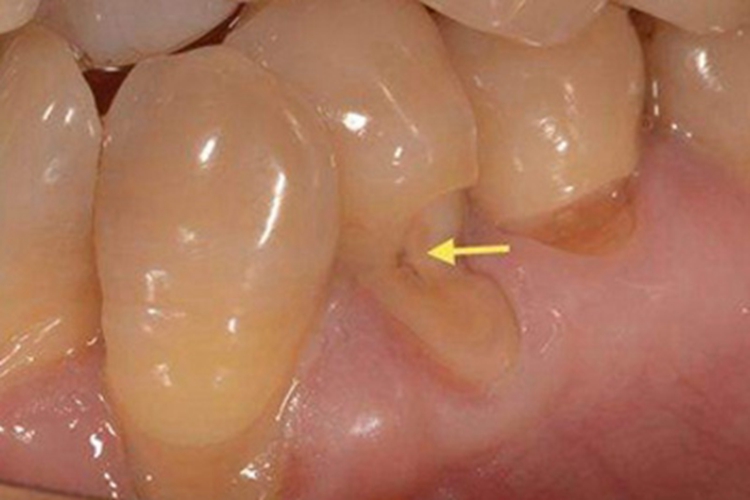

楔状缺损的损害集中发生在牙齿,临床上可表现为患者的部分牙齿存在明显的缺损,口大底小呈凹陷的坑样,可以看到裸露在外的深部组织,缺损的边缘相对较整齐,患者会有明显的疼痛。